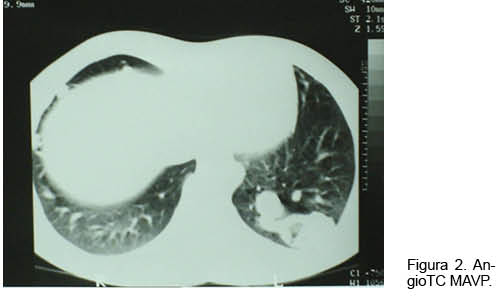

Hombre de 18 años con historia de epistaxis recurrentes y cianosis desde la infancia. Del examen clínico se destacaba: saturación arterial de oxígeno (SaO2) de 80%, mucosas hipercoloreadas e hipocratismo digital (Figura 1). La paraclínica confirmó poliglobulia e insuficiencia respiratoria severa, sin corrección con la administración de oxígeno. La RxTx evidenció una opacidad tenuemente homogénea en la región paracardíaca izquierda. El ecocardiograma descartó alteraciones estructurales. Se realizó angioTC con reconstrucciones 3D (Figura 2), confirmándose dos MAV, una de aspecto nodular, en el lóbulo superior del pulmón derecho, y otra más voluminosa, en la base del pulmón izquierdo (Figura 3). En esta última la arteria que la nutría continuaba la rama lobar inferior izquierda, siendo casi del mismo calibre y drenando en la vena pulmonar inferior. Se observaban múltiples dilataciones vasculares periféricas, bilaterales de aspecto varicoso. Se realizó embolización durante la arteriografía pulmonar con varios “coils” fibrilares de platino. La gasometría de control reportó una presión arterial de oxígeno (PaO2) de 79 mm Hg y una SaO2 de 96%.